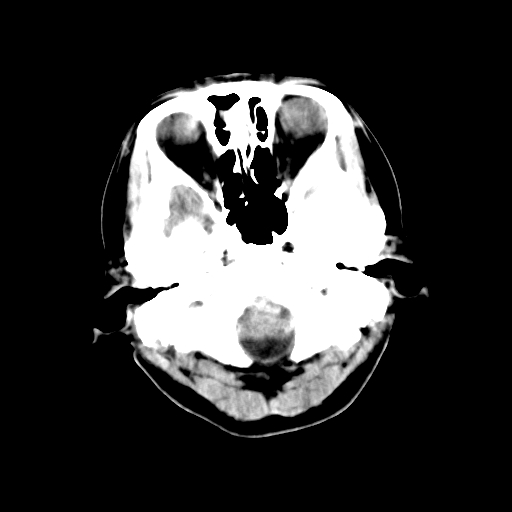

猜一个:左枕骨嗜酸性肉芽肿?但不具膨胀性,难说

考虑枕骨血管瘤

颅内未见明显异常,枕骨松质骨瘤可能性大。颅骨板障起源骨瘤较常见,骨血管瘤有垂直骨针及粗大钙化,嗜酸性肉芽肿软组织有改变,典型者可见“纽扣状”死骨,年龄通常较小。

以下是引用深泽交通医院在2010-1-6 9:04:00的发言:[br]考虑枕骨血管瘤

左枕骨松质骨不均匀低密度灶,边缘清楚,考虑良性松质骨性骨瘤可能性大。

以下是引用sunbin在2010-1-6 14:39:00的发言:[br]左枕骨松质骨不均匀低密度灶,边缘清楚,考虑良性松质骨性骨瘤可能性大。

不排除左枕骨嗜酸性肉芽肿可能。